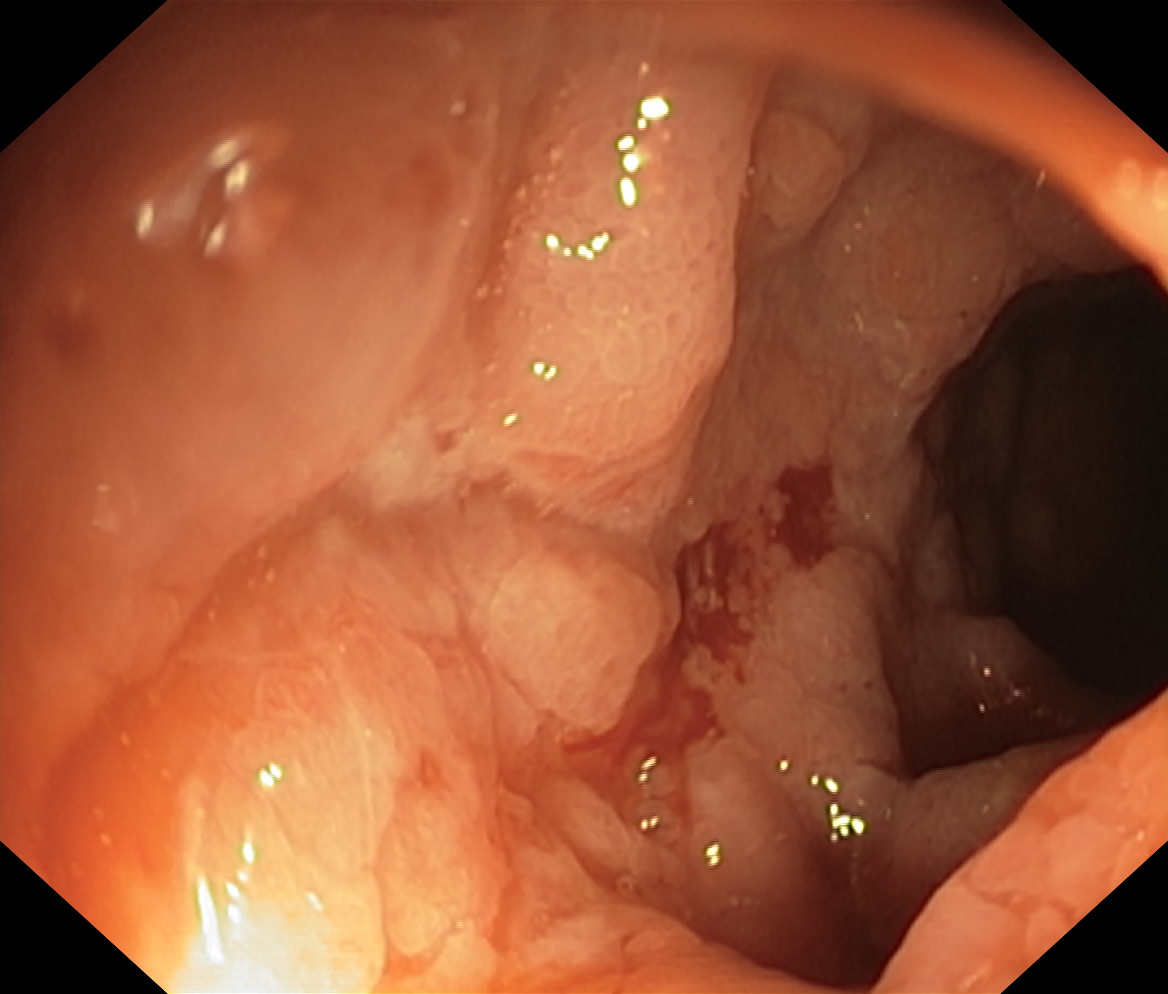

Choroba Leśniowskiego-Crohna